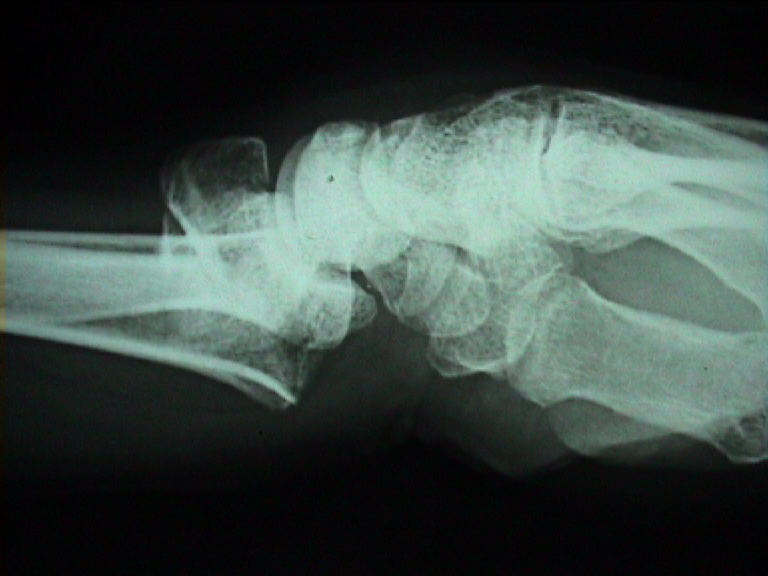

Arztbrief